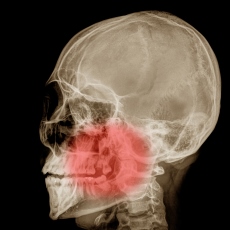

Your jaw is a set of bones that holds your teeth. It includes:

- The maxilla, which is the upper part of your jaw. It holds your top teeth in place and doesn't move. It also supports the muscles involved in chewing and facial expressions.

- The mandible, which is the lower part of your jaw. You move it when you talk or chew. It also holds your lower teeth in place.

- The temporomandibular joints (TMJs), which are two joints (one on each side) that connect your mandible to your skull.

Diagnostic imaging tests are often used to diagnose jaw injuries and disorders. Your treatment will depend on which jaw problem you have.